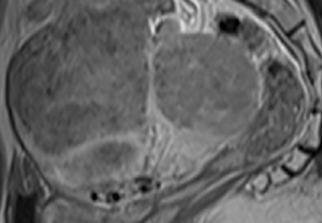

자궁근종 비수술 하이푸 치료 후 분만사례입니다. 자궁근종 하이푸 치료는 자궁근종 부위만 선택적으로 치료하는 시술로 자궁근종 전체적으로 시술하였습니다. 8cm 액화변성 자궁근종 하이푸 치료 시간은 57분이...